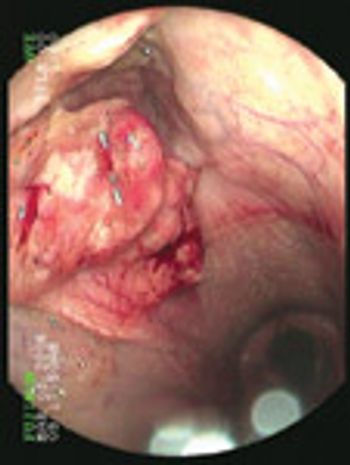

A multitude of diseases can cause pruritus in the cat, from infectious diseases to allergic diseases to neoplasia.

What do you do with those dogs that have been diagnosed with atopy but are not getting better or better enough with treatment? Unfortunately, there are no magic potions either from the past or present that are going to easily fix these patients. Owners of these dogs need to understand some basic concepts about pruritic diseases. First, pruritus is a common presenting sign for both allergic and non-allergic dermatopathies. Second, your long term goal is not necessarily to stop the itch completely, but to decrease it to a level comfortable for both the client and the patient. Third, pruritic diseases are not mutually exclusive. This means that the same patient can have 3 or 4 different problems that make him itch.